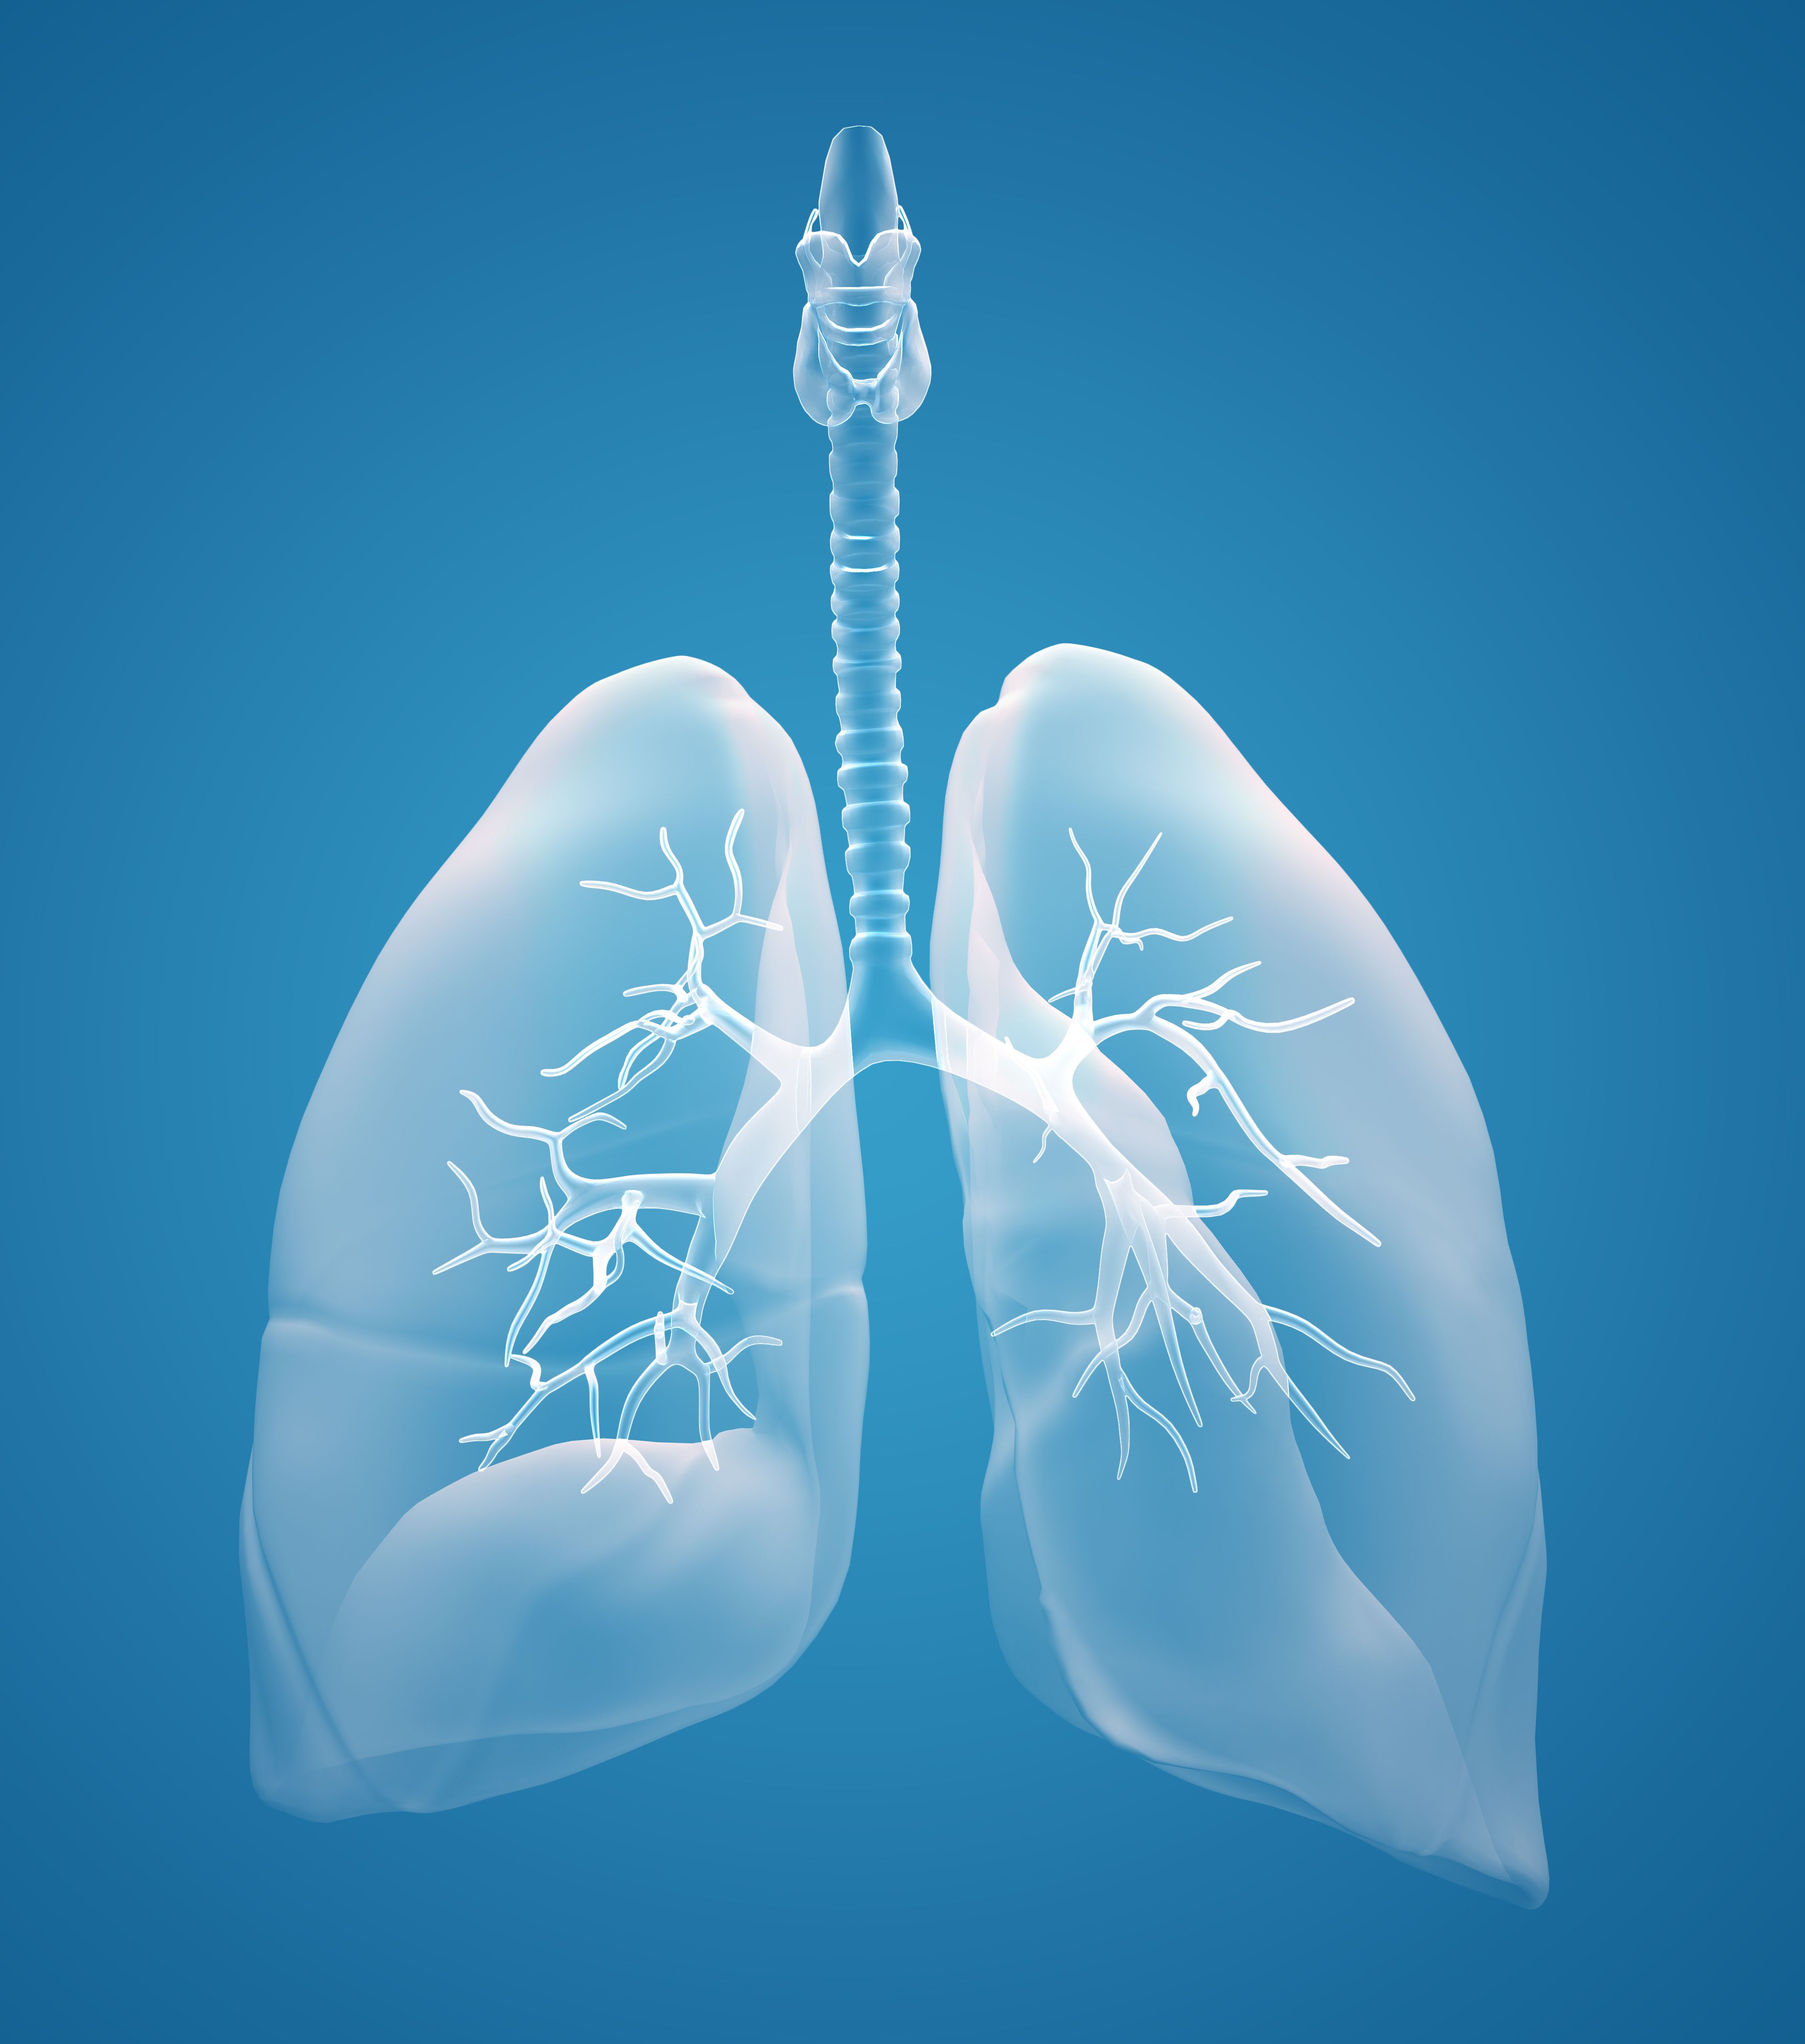

Лёгкие человека: Учебные картинки для детей